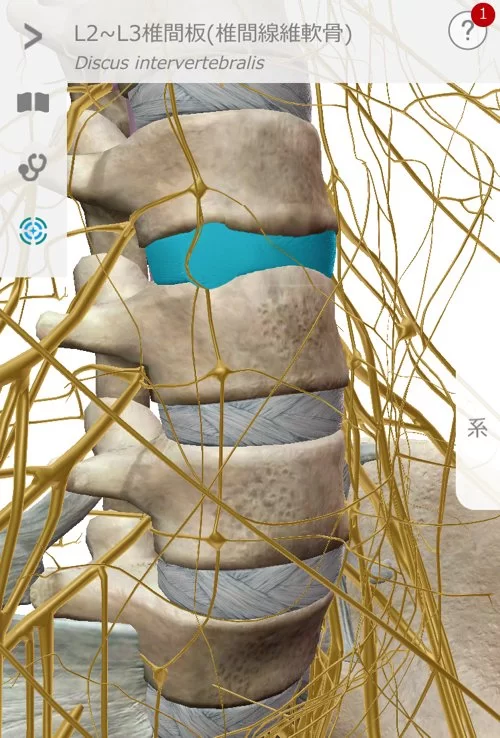

そもそもヘルニアとは?

椎間板ヘルニアに関して簡単に説明すると

こんな感じで骨と骨の間に軟骨があります。

そして腰骨の周りには神経がいっぱい走っているのです。

そんな場所でこんな感じで軟骨が飛び出して神経に触れると

痛みやシビレが出る。それが一般的なヘルニアだと思って下さい。